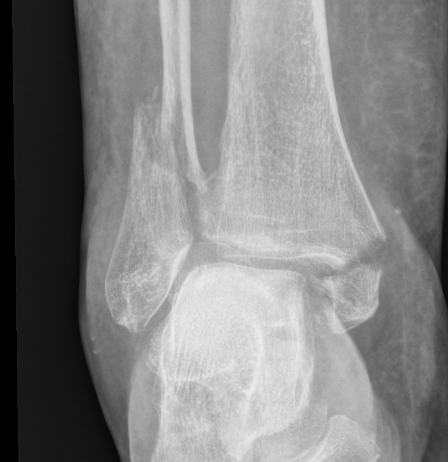

| Bimalleolar fractures | Trimalleolar fractures |

Fibular + medial malleolus Fibular + posterior malleolus |

Fibular + Medial malleolus + Posterior malleolus |

Bimalleolar fractures

Medial malleolus + Weber B lateral malleolus

Medial malleolus + Weber C lateral malleolus

Tri-Malleolar Fracture

Lateral malleolus + medial malleolus + posterior malleolus